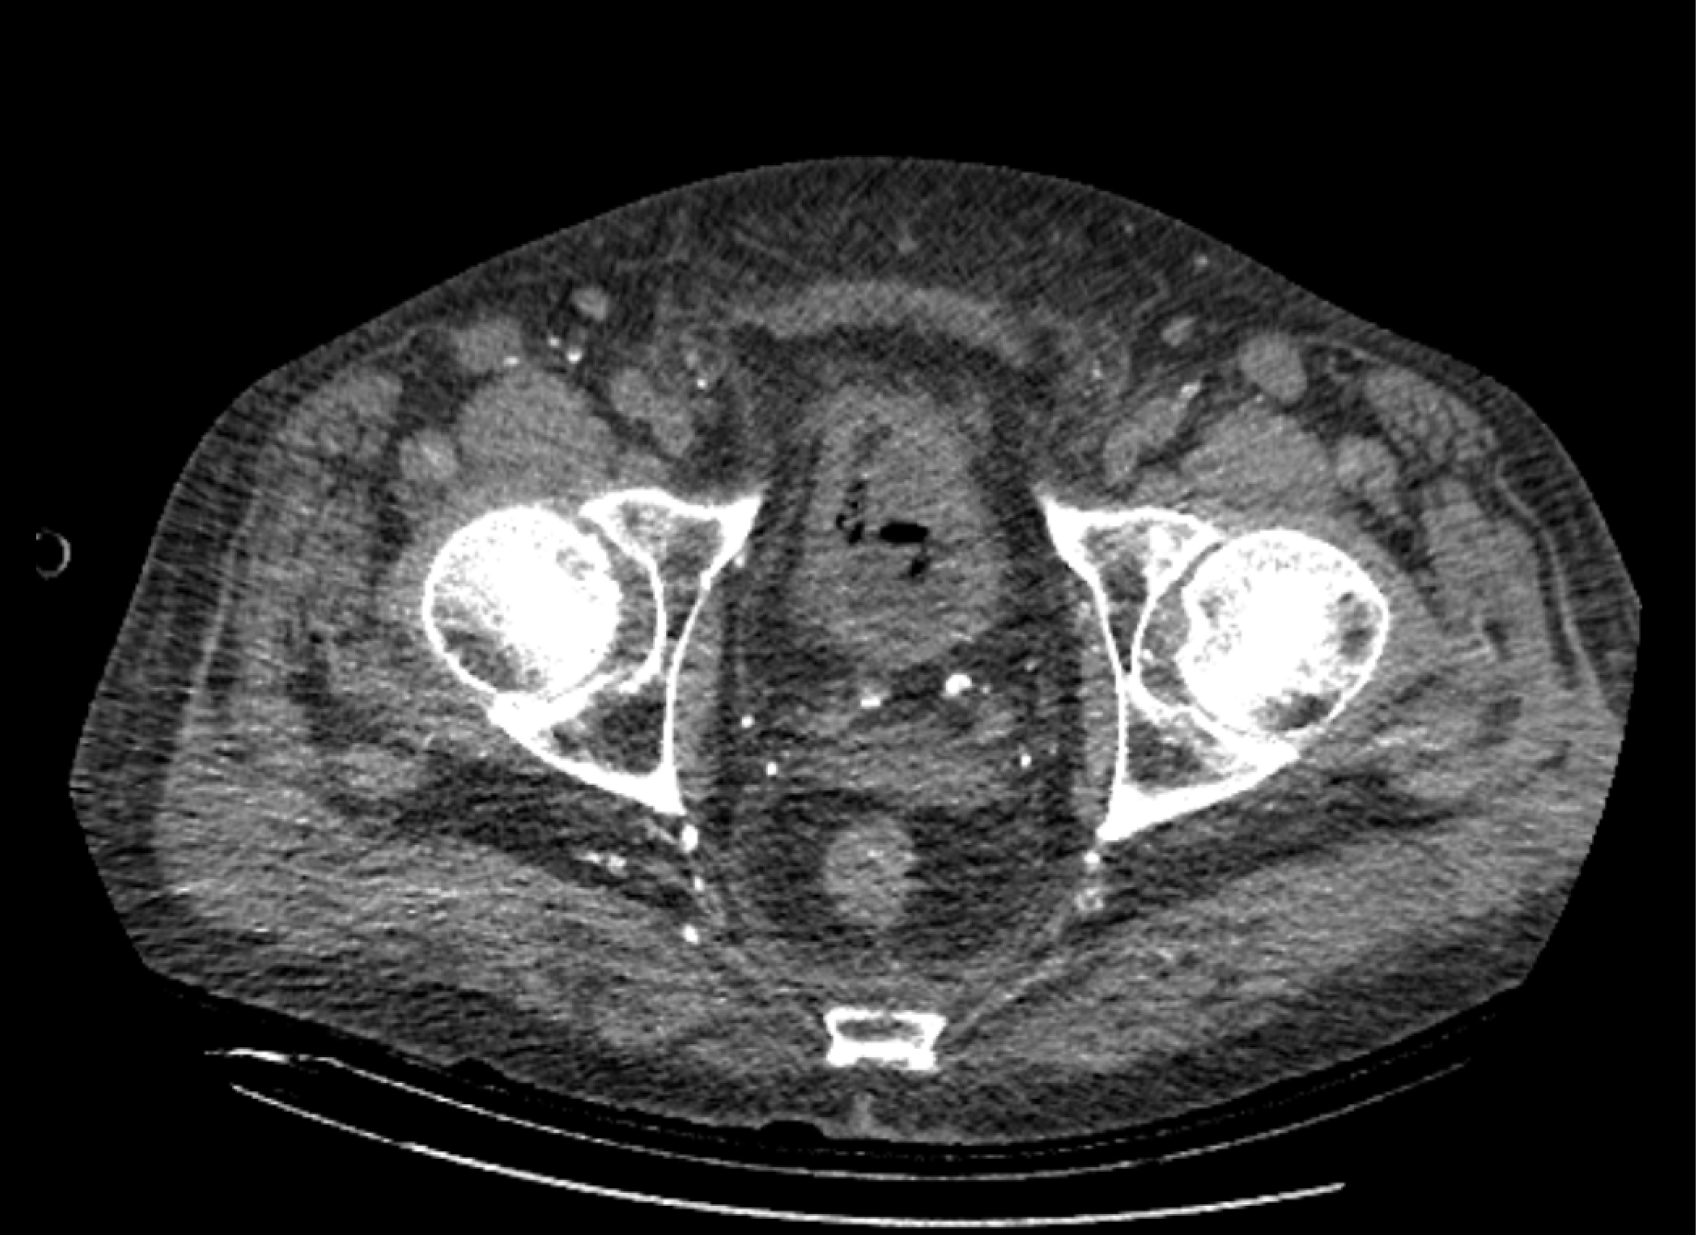

На следующий день состояние пациента оставалось тяжелым, с отрицательной динамикой, креатинин сыворотки возрос до 735,2 ммоль/л, Появились жалобы на слабость, тошноту. При осмотре: живот мягкий, вздут по всем отделам, при пальпации болезненный. Область почек не изменена, при пальпации безболезненна, патологических изменений в области почек не выявлено. Симптом поколачивания отрицательный билатерально. При УЗИ были обнаружены плевральный выпот по 300–400 мл с каждой стороны, гепатомегалия, увеличение размеров селезенки, асцит. Кроме того, в обеих почках были визуализированы тени, характерные для конкрементов. По данным компьютерной томографии (КТ) конкрементов не обнаружено, но в лоханке, на всем протяжении левого мочеточника и, частично, в правом мочеточнике, а также в мочевом пузыре визуализировался газ (рис. 1–6).

Рис. 1. Компьютерная томография органов брюшной полости, забрюшинного пространства, органов малого таза. Газ в мочевом пузыре

Рис. 2. Компьютерная томография органов брюшной полости, забрюшинного пространства, органов малого таза. Газ в мочевом пузыре